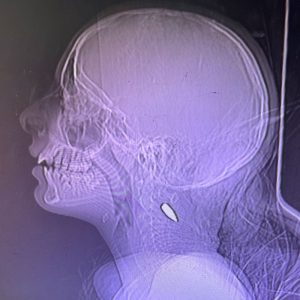

(গাজায় শিশুদের গলা এবং মাথায় shrapnel-এর টুকরো)